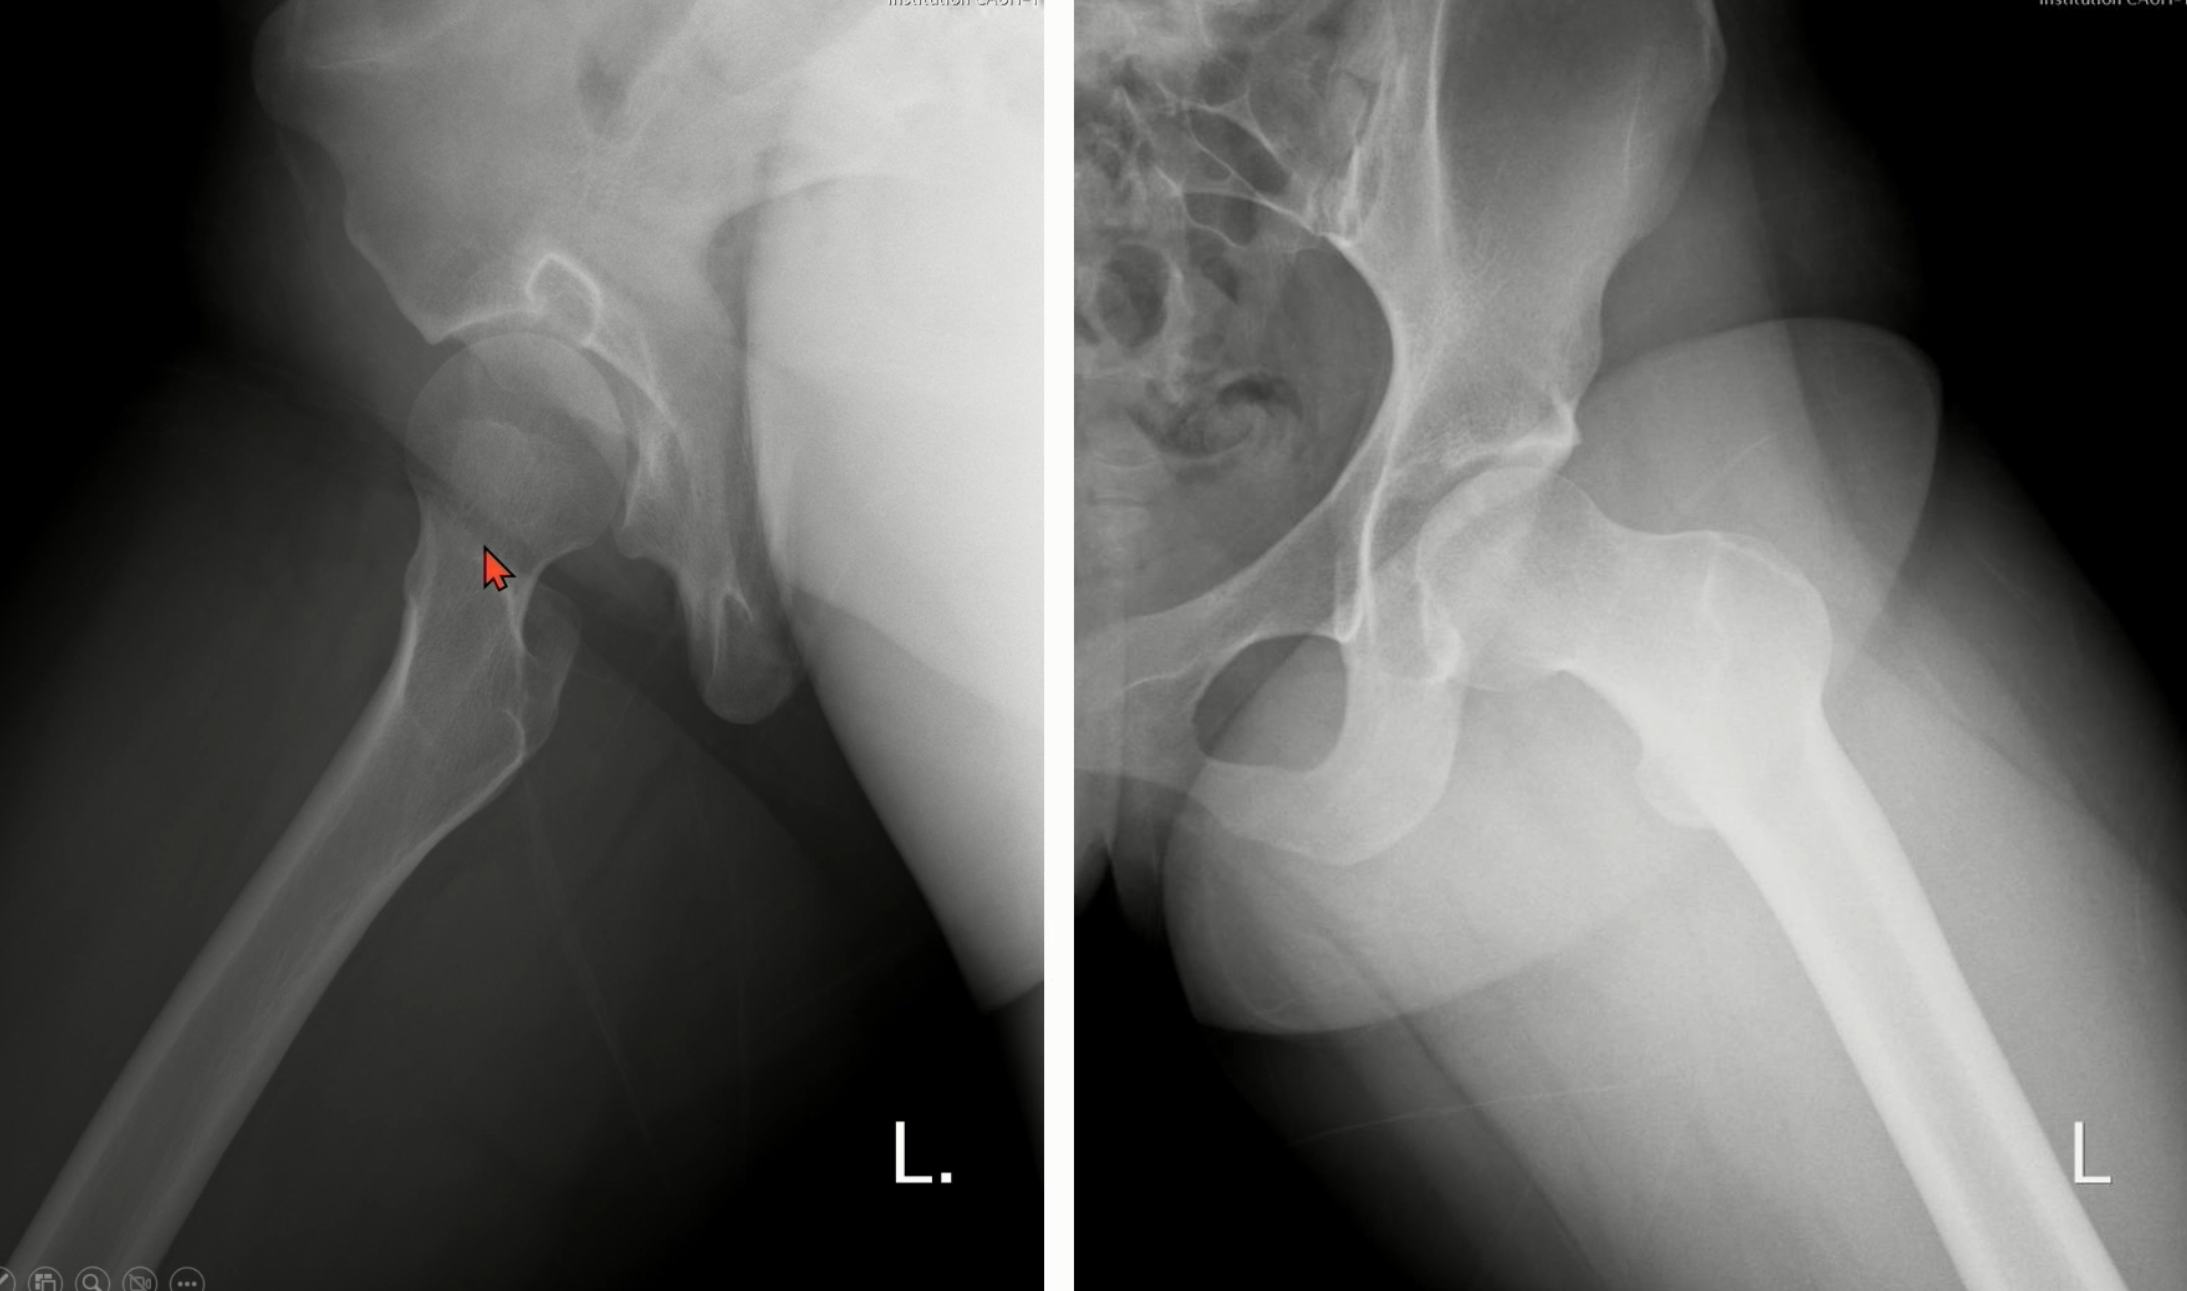

Axial 또는 modified dunn view에서 femur의 head와 neck의 사이에서 bump로 관찰됩니다.

(빨간 화살표)

CT나 MRI에서는 더 확실하게 볼 수 있습니다.

head/neck junction 부위에 cyst나 bump가 보이며, head의 구형이 소실된 모습을 볼 수 있습니다.

Case1)